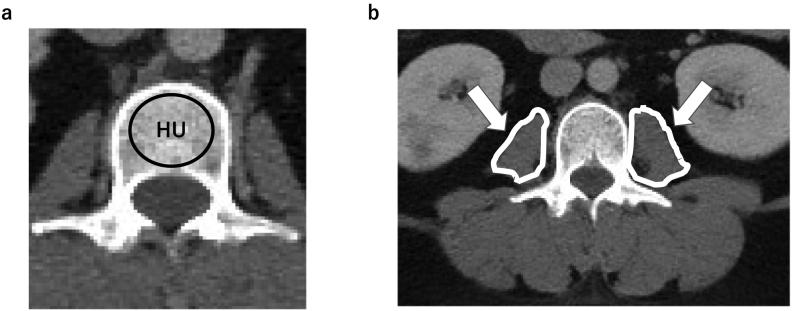

Sleeve gastrectomy is the most common surgical procedure to reduce weight and treat metabolic complications in patients with moderate-to-severe obesity; however, it affects the musculoskeletal system. Dual-energy X-ray absorptiometry (DXA), which is commonly used to measure bone mineral density (BMD), may be affected by excess fat tissue around the bones, interrupting BMD measurement. Due to the strong correlation between DXA and the Hounsfield units (HU) obtained from computed tomography (CT) scans, BMD assessment using clinical abdominal CT scans has been useful. To date, there has been no report of detailed CT evaluation in patients with severe obesity after sleeve gastrectomy.

This study investigated the effect of sleeve gastrectomy in severely obese patients on bone and psoas muscle density, and cross-sectional area using retrospective clinical CT scans.

This was a retrospective observational study that included 86 patients (35 males and 51 females) who underwent sleeve gastrectomy between March 2012 and May 2019. Patients' clinical data (age at the time of surgery, sex, body weight, body mass index (BMI), comorbidities, and preoperative and postoperative blood test results, HU of the lumbar spine and psoas muscle and psoas muscle mass index (PMI)) were evaluated.

The mean age at the time of surgery was 43 years, and the body weight and BMI significantly reduced ( < 0.01) after surgery. The mean hemoglobin A1c level showed significant improvement in males and females. Serum calcium and phosphorus levels remained unchanged before and after surgery. In CT analysis, HU of the lumbar spine and psoas muscle showed no significant decrease, but PMI showed a significant decrease ( < 0.01).

Sleeve gastrectomy could dramatically improve anthropometric measures without causing changes in serum calcium and phosphorus levels. Preoperative and postoperative abdominal CT revealed no significant difference in the bone and psoas muscle density, and the psoas muscle mass was significantly decreased after sleeve gastrectomy.